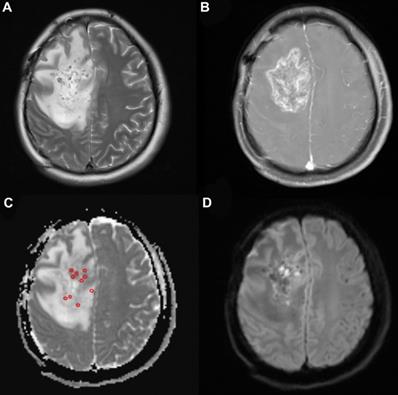

Figure 2

A 33-year-old woman with high-grade glioma (WHO grade IV). (a) Pre-125I implantation T2WI, (b) contrast-enhanced T1WI, (c) ADC map (circles indicate the ADC values measured on the ADC map), and (d) DWI showing the glioma location in the brain. The minimum ADC value was detected on the ADC map.

ADC maps were constructed via software installed on the MR unit. Two radiologists with 17 and 10 years of experience who were both blinded to the research identified the solid tumor components with or without enhancement on the MRI images in consensus. Five to ten regions of interest (ROIs) were manually placed within the solid tumor component on the ADC map by the above two radiologists. No cystic or necrotic areas or skull, which may influence the ADC values, were allowed to cover the ROI. minADC values were obtained for further analysis.

Table 1 shows the baseline characteristics of the patients with primary and recurrent glioma. Twenty-three patients (16 male and 7 female) were included in the present study. Four patients were over 65 years old. The median KPS (Karnofsky performance score) was 80 (range, 50-90). Of the patients with recurrent glioma, 12 underwent gross total resection and 2 underwent partial resection before. Eleven of the patients received radiotherapy with a total median radiation dose of 60 Gy (range: 30-64.2 Gy) and chemotherapy with temozolomide (TMZ) using the Stupp protocol. There were 3 patients who rejected radiochemotherapy after resection. Nine patients with primary glioma had MRI- and CT-proven high-grade glioma and received 125I brachytherapy as their initial treatment rather than conventional therapy with their informed consent due to extensive lesions, poor medical conditions or the rejection of surgery and adjuvant radiochemotherapy. Biopsy was performed during the 125I implantation to confirm the diagnosis. Minimum ADC values were obtained from the ADC map (Fig. 2). The mean minADC value was 0.96. The number of patients with tumors located in the left hemisphere, right hemisphere, both hemispheres and the cerebellum was 10, 9, 3, and 1, respectively. The median volume of the tumor was 37.33 cm3. Aggravating brain edema was found in seven of these patients, which was relieved after dehydration treatment approximately 15 days later. No severe postoperative complications were found in these patients.